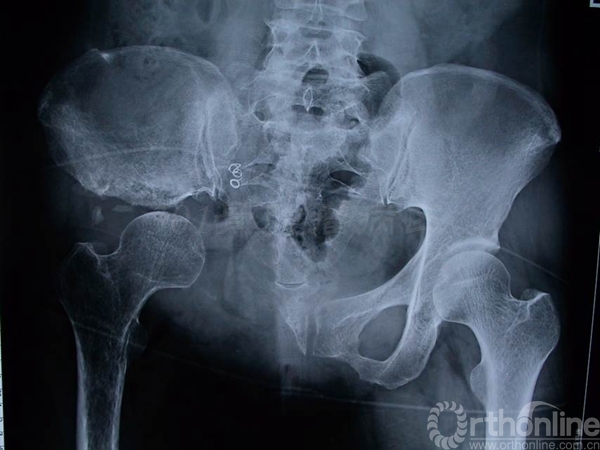

术后13年X线片